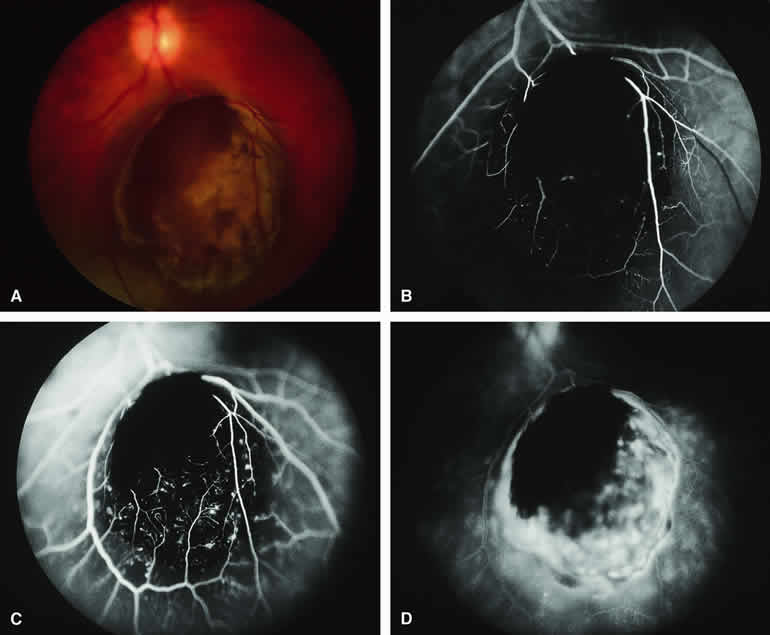

Amelanotic Choroidal Nevus

Approximately 10% to 15% of choroidal nevi are largely or completely amelanotic clinically. Fluorescein and ICG angiography of an amelanotic choroidal nevus (see Fig. 3) tend to show less prominent hypofluorescence of the lesion than they do with darkly melanotic nevi. Because of the lack of intracellular melanin pigment within the nevus cells, some large-caliber choroidal blood vessels running through the nevus may be visible in the region of the mass (see Fig. 3B and C). These choroidal blood vessels are better defined by ICG angiography than by fluorescein angiography. Amelanotic choroidal nevi often appear mildly hyperfluorescent in late-phase frames (see Fig. 3D).